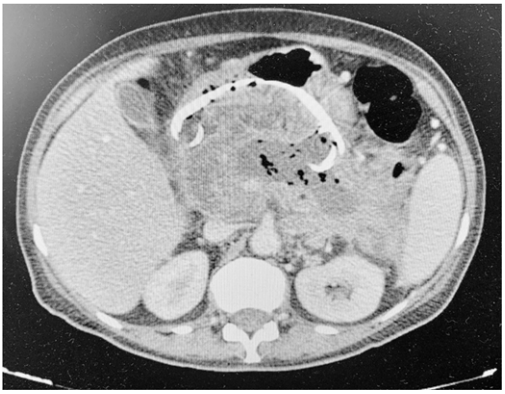

Um paciente, que apresentava pancreatite aguda necrótica complicada há seis semanas, foi submetido a um tratamento.

Com base nesse caso hipotético, é correto afirmar que o exame de controle imediato mostrado acima foi realizado após um tratamento